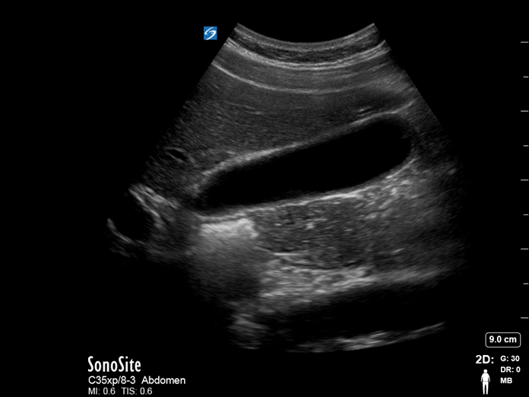

Gallbladder Full with Bile Image